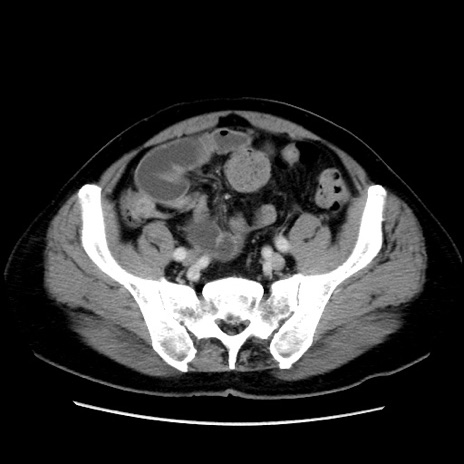

症例16(横断像)

【症例】 70歳代男性

【主訴】 腹痛、嘔吐

【現病歴】 約1ヶ月前より間欠的に腹痛と嘔吐あり、当院消化器内科を受診したところCTで多発する肝臓のLDAを指摘され、精査中であった。以降は消化器症状は安定していたが、2日前より嘔気と腹痛があり、同日より排便・排ガスが消失した。改善認めず、 本日、救急外来を受診した。

【既往歴】 大腸ポリープ切除後。

【身体所見】意識清明・会話良好、BT 36.3℃、BP 127/80mmHg、 P 80bpm、腹部:膨満あり、平坦・軟、上腹部正中および下腹部正中に圧痛あり、反跳痛なし、筋性防御なし。

【データ】WBC 7200、CRP 0.77